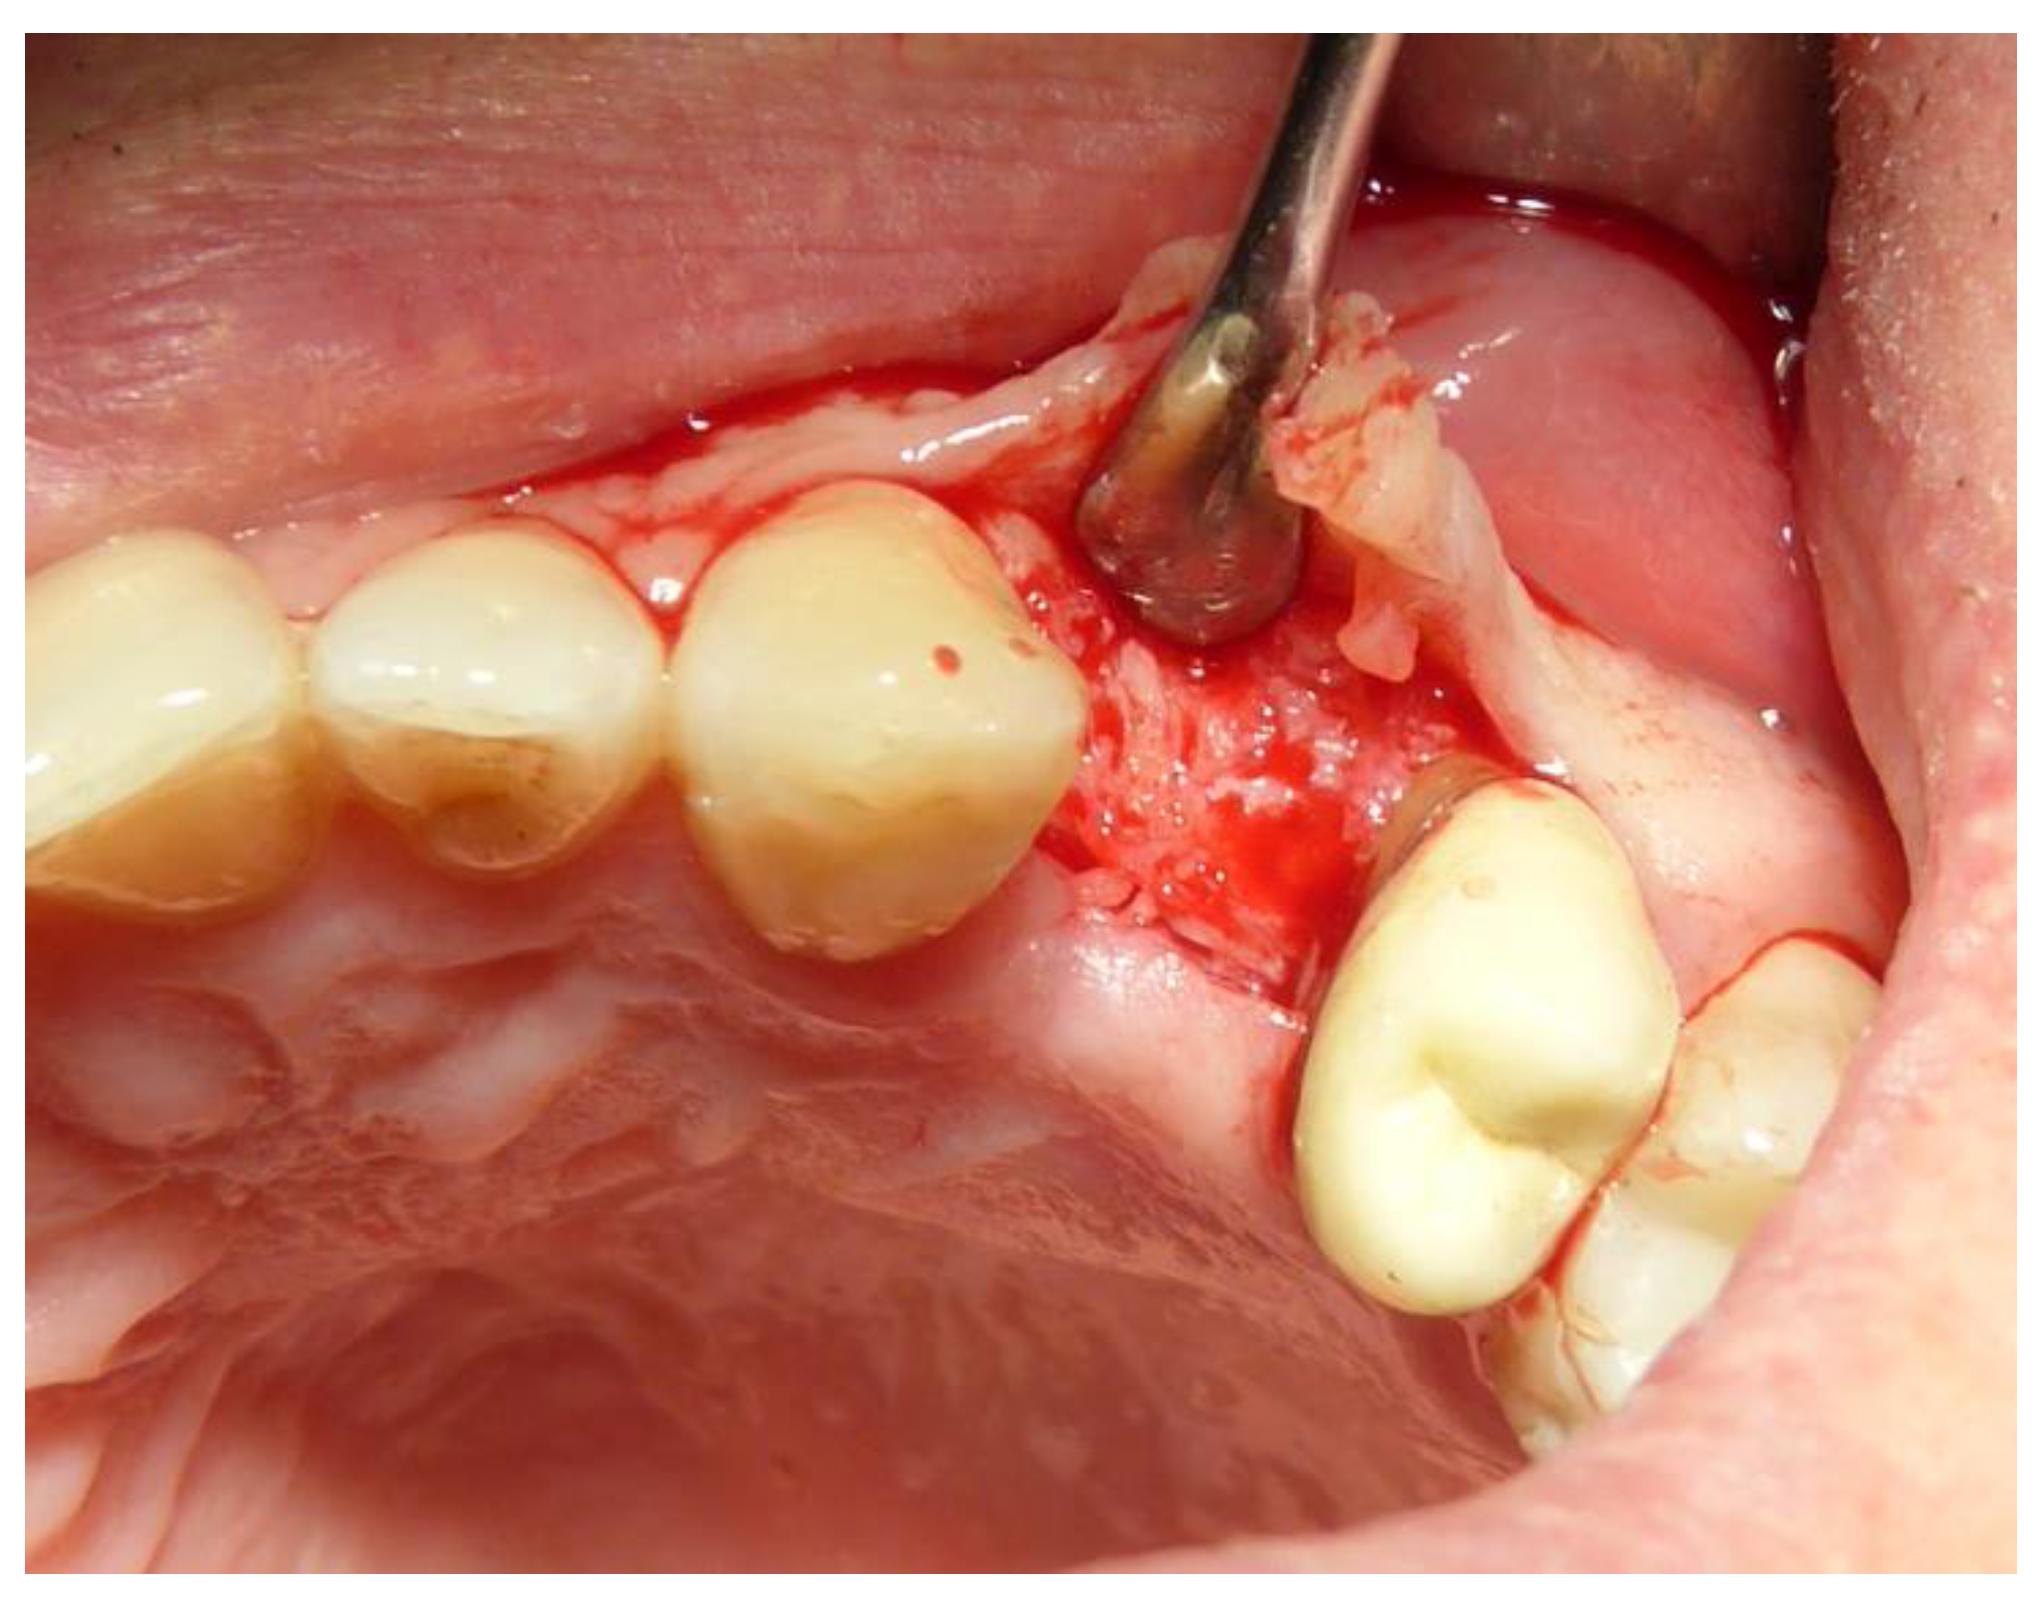

- Subjects who underwent surgical intervention for tooth removal and alveolar socket preservation using exclusively a tooth-derived bone substitute (Tooth Transformer®—Tooth Transformer SRL).

2.3. Preoperative and Surgical Procedures